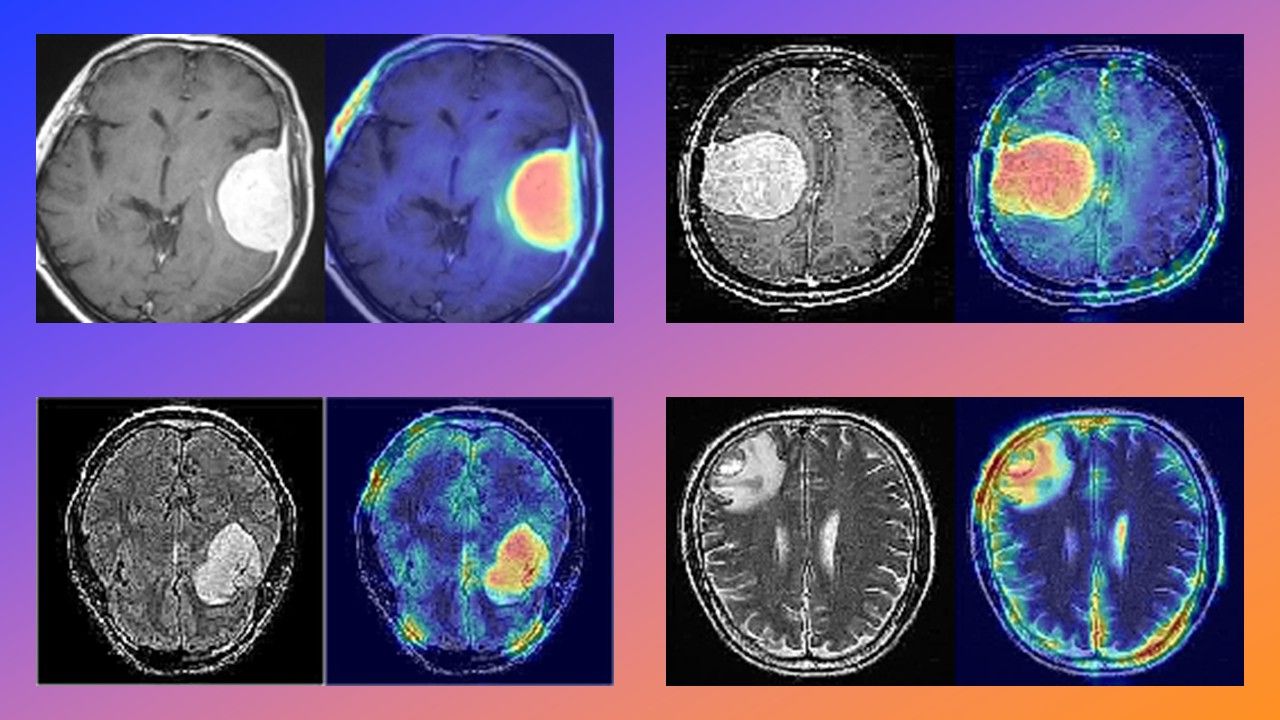

La detección de tumores cerebrales es uno de los desafíos más complejos de la medicina moderna. Si bien la Resonancia Magnética (MRI) es la herramienta de diagnóstico estándar, el análisis manual requiere mucho tiempo. Como desarrolladores, nos preguntamos: ¿podemos automatizar esto con precisión y explicabilidad? Introducción En este proyecto, me alejé de las Redes Neuronales… Lee más

Aprendizaje Profundo para Imágenes Médicas: Detección de Tumores Cerebrales con Autoencoders